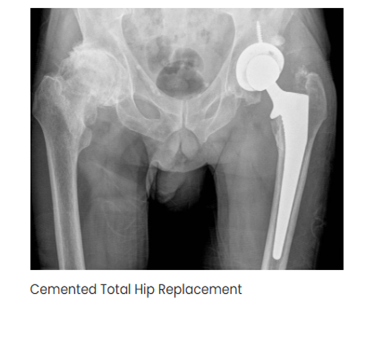

- Types of Hip Replacement Surgeries we offer

- Total Hip Replacement (THR) Unilateral & Bilateral

- Complex Revision Hip Surgery

- Robotic / Computer-Assisted Hip Replacement